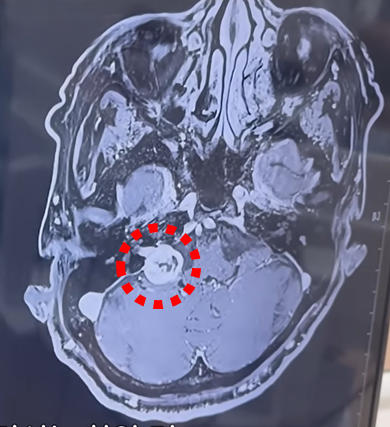

방사선 수술은 어떻게 작동하나?

일반 방사선 치료와 달리 고용량을 짧은 기간에 집중적으로 쏜다.

종양의 DNA를 파괴해 성장 불능 상태로 만든 뒤 죽은 조직은 그 자리에 그대로 남아있고 이후 추적 검사로 커지지 않는지 확인한다.